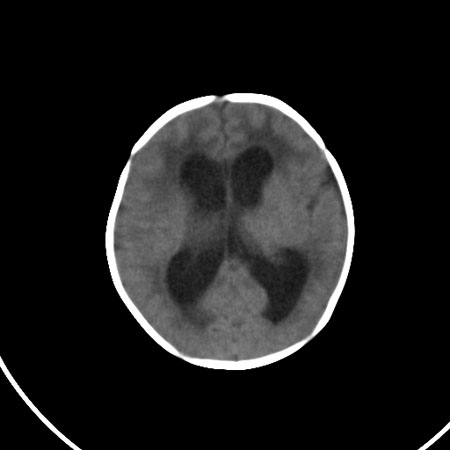

以下是引用小初学者在2009-1-10 17:51:00的发言:[br]考虑缺血缺氧性脑病后遗性改变。

以下是引用拾荒者在2009-1-10 19:23:00的发言:[br]生后有蛛网膜下腔出血病史,现幕上脑室明显扩张,脑室周围白质局限性密度减低,考虑hie脑病后遗表现。